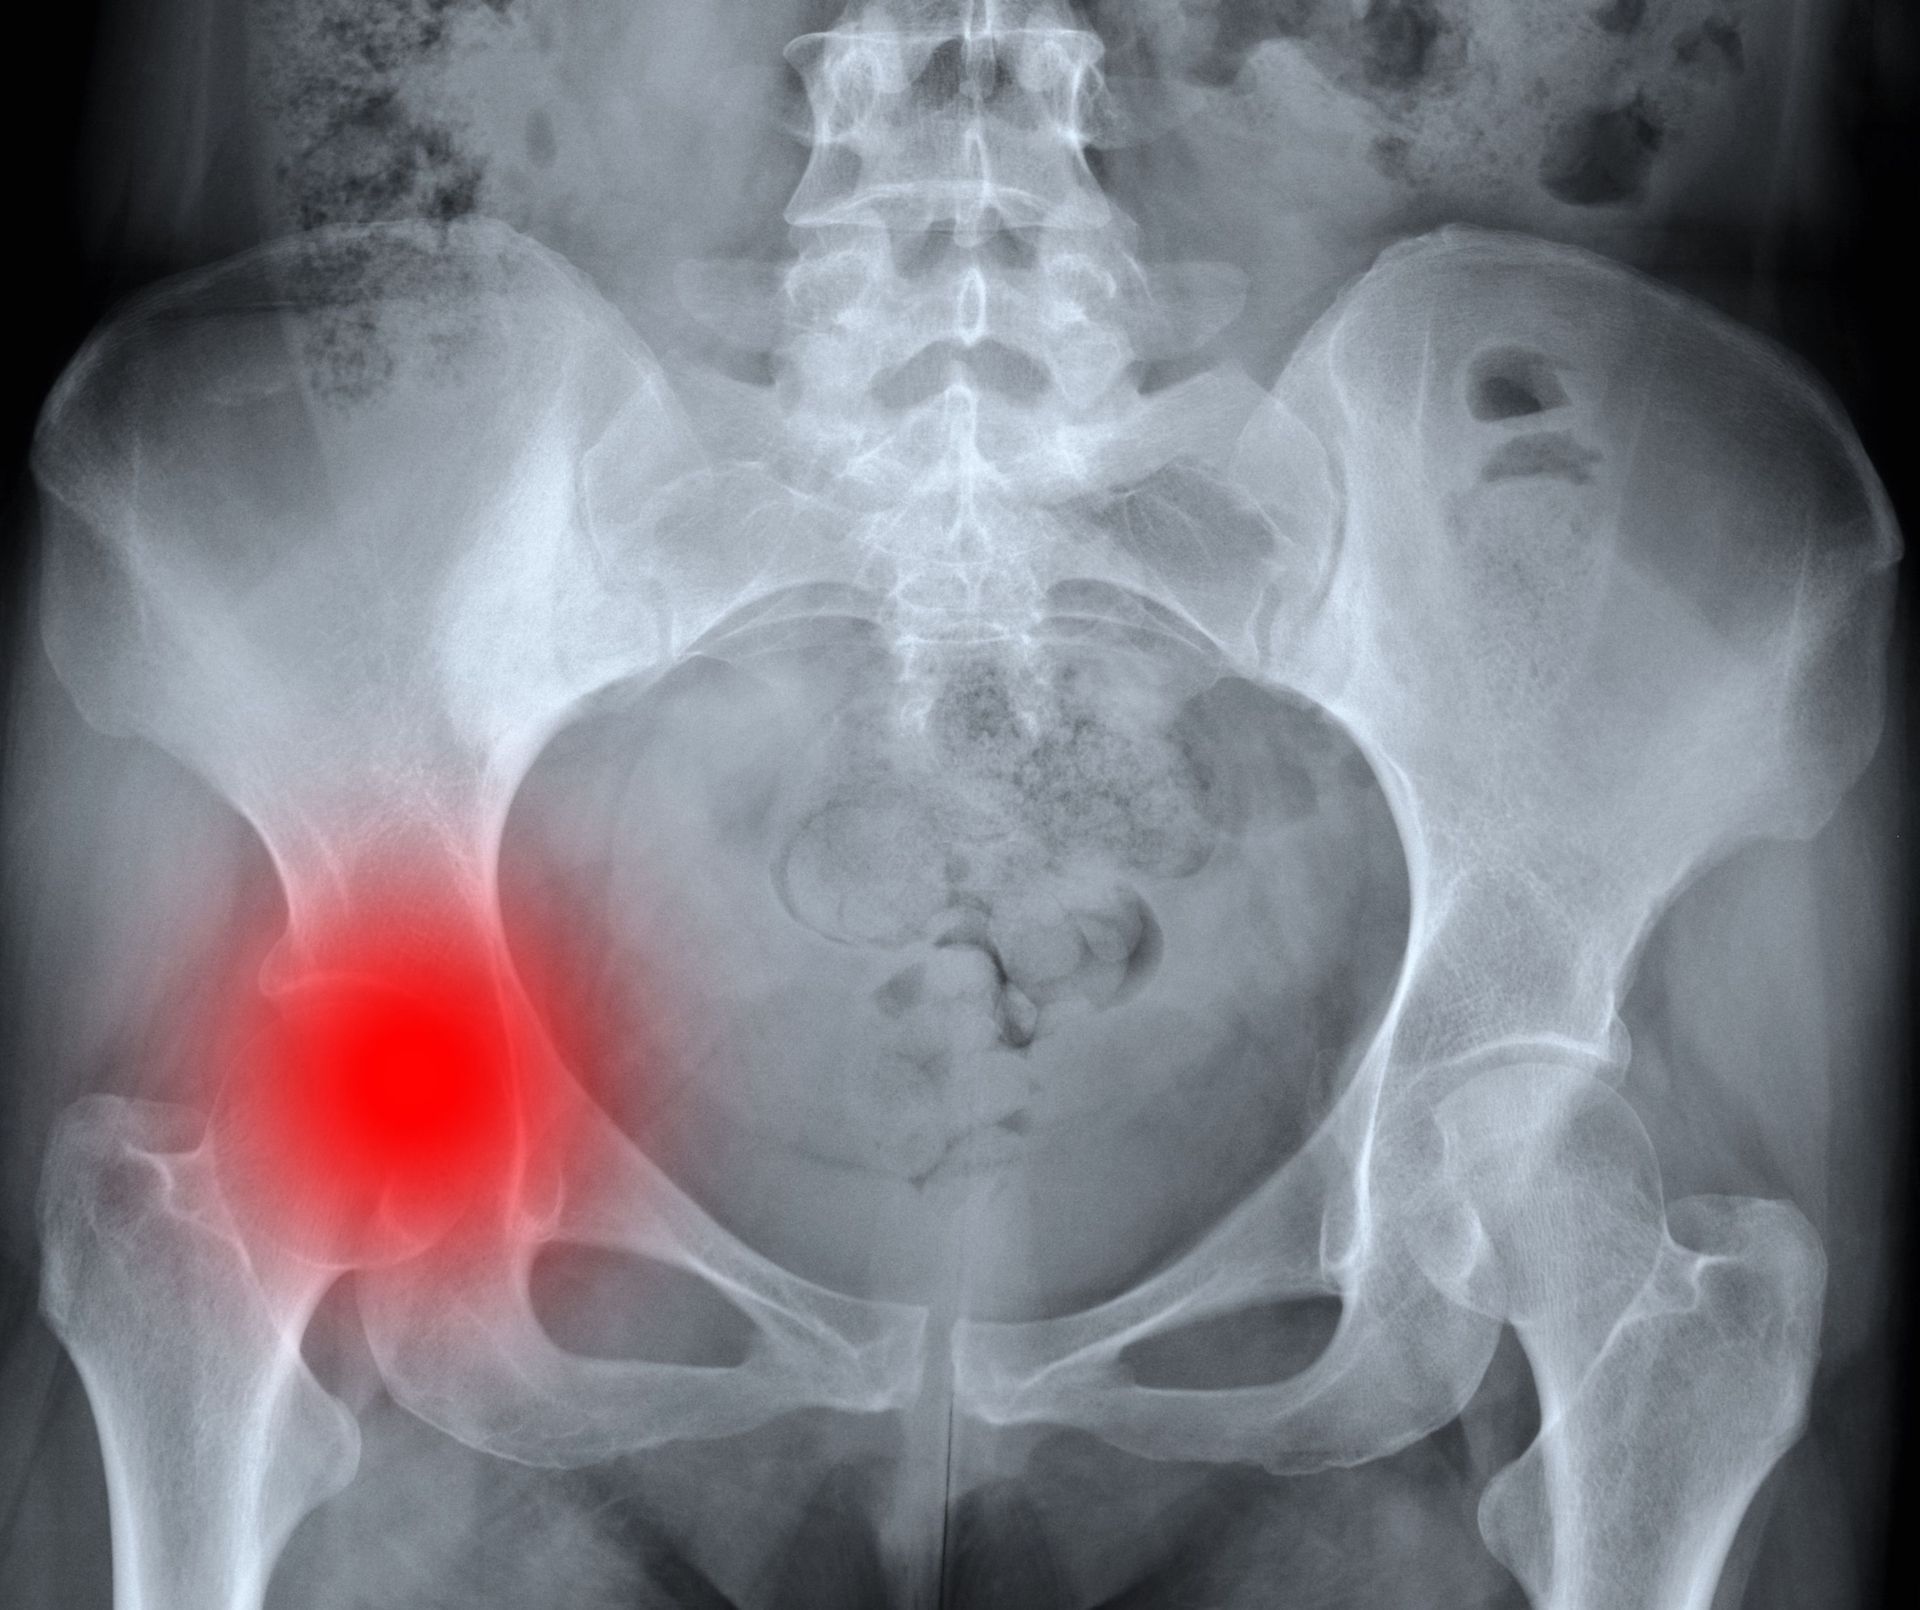

If you sustain an injury to your hip, it’s important to visit Benton Franklin Orthopedic Associates to get an accurate diagnosis as there are many possible causes, most of which require expert treatment to heal properly.

What injuries are most likely to cause hip pain?

• Arthritis

• Femoral Acetabular Impingement (FAI and Cam Lesions)

• Hamstring tears

• Labral tears

• Trochanteric Bursitis

How is hip pain treated?

• Hip arthroscopy

• Partial hip replacement

• Therapeutic injections

If conservative treatment options aren’t improving your knee condition, surgery is also an option. The team at Benton Franklin Orthopedic Associates has particular expertise in performing highly specialized, minimally invasive hip replacement. If you’re suffering from hip pain, book an appointment today.